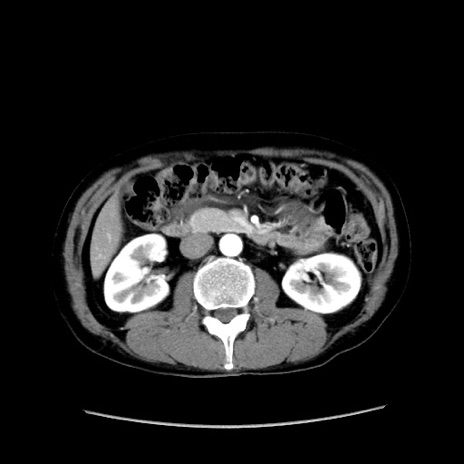

症例37(横断像)

【症例】40歳代 男性

【主訴】腹痛

【現病歴】4時間ほど前に電車に乗車中に臍部上より腹痛出現。徐々に増悪し起立困難となり、救急外来受診。生ものは数日食べていない。今朝お雑煮を食べた。

【身体所見】BT 36.8℃、BP 117/84mmHg、HR 91/min、SpO2 97%、苦悶様、腹部:臍上部広範囲圧痛あり、反跳痛±

【データ】WBC 8100、CRP 0.03